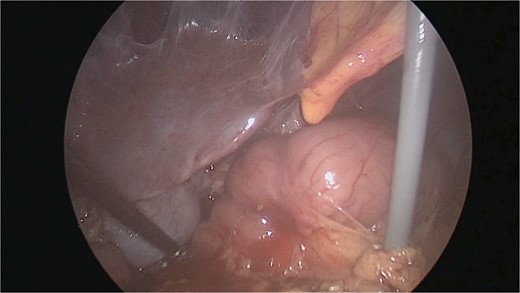

There were extensive perihepatic adhesions with involvement of the subhepatic space (Fig. 3). The initial intraoperative assessment was that this inflammation was secondary to a prior cholecystitis, but subsequent dissection revealed a pristine gallbladder (Fig. 4) with inflammatory adhesions in the pyloro-duodenal region (Fig. 5). All adhesions encasing the duodenum were lysed and the duodenum was kockerized (Fig. 6).

The gallbladder was dissected free of the dense adhesions. There was no evidence of previous cholecystitis. The stomach (short arrow) was spared of adhesions, but the first and second parts of the duodenum were encased (long arrows).